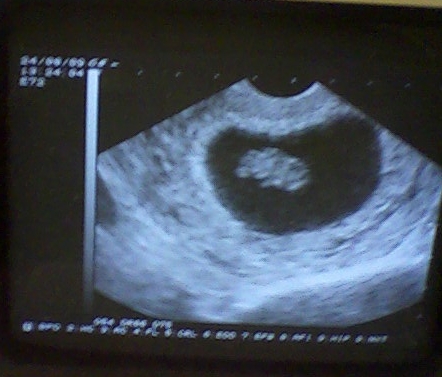

Tök jó az uh.kép, hány hetes és napos az uh kép??????

Tökjó a kép! picikét irigyellek is érte...én is szeretnék ilyet!!! :D